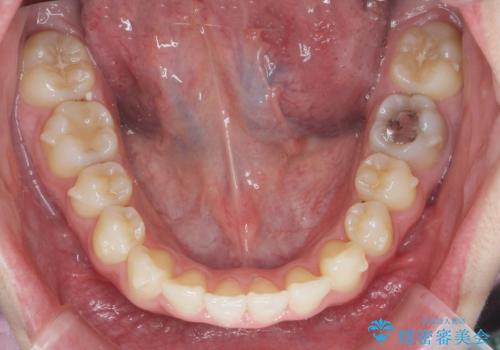

- 出っ歯のように見える前歯の角度を治したい、と矯正治療を希望され来院されました。

抜歯をせずにマウスピース矯正システムインビザラインを用いてしっかりと前歯の角度を改善していきます。

前歯の角度だけでなく内側に倒れ込んでいた奥歯もしっかり起こすことで咬合関係も理想的に仕上げています。